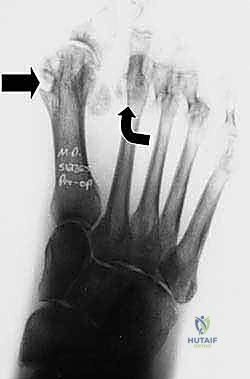

مع تقدم المرض واستمرار الالتهاب (التهاب الغشاء الزليلي - Synovitis)، يحدث تمدد وضعف في الأربطة الداعمة والمحفظة المفصلية، مما يؤدي إلى فقدان الاستقرار المفصلي. النتيجة الحتمية لذلك هي ظهور تشوهات مؤلمة ومحددة تجعل من مجرد الوقوف أو المشي أو حتى ارتداء الأحذية العادية عذاباً يومياً للمريض. من أبرز هذه التشوهات الانحراف الشديد لإصبع القدم الكبير (Hallux Valgus)، وتراكب أصابع القدم الصغرى، وبروز رؤوس عظام المشط أسفل القدم مما يسبب تقرحات ومسامير لحمية مؤلمة جداً.

- تغير شكل القدم: انحراف إصبع القدم الكبير نحو الأصابع الأخرى بحدة (وكأنه يركب فوقها أو تحتها).

| مفصل الإصبع الكبير | مستقر ومستقيم | انحراف شديد (Hallux Valgus) |